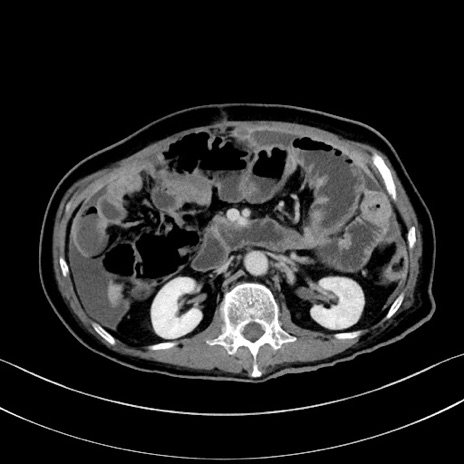

冠状断像

【症例】60歳代男性

【主訴】嘔吐

【現病歴】胃癌にて胃全摘後。食思不振が悪化し、夜中に嘔吐することがある。

【既往歴】胃癌、胃全摘、脾摘、胆摘後

【データ】WBC 5900、CRP 10.56